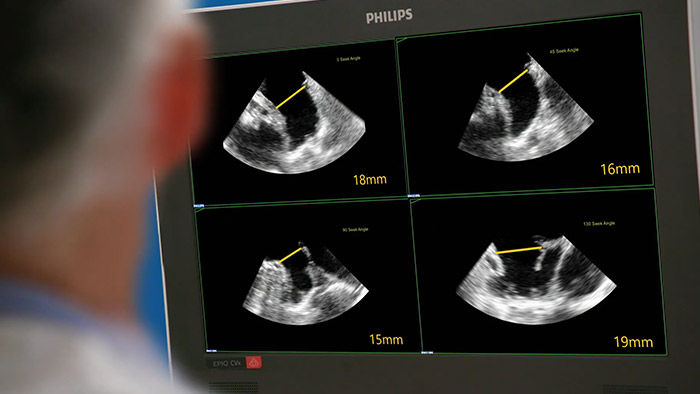

Valutazione veloce, facile e intuitiva dell’auricola sinistra. La soluzione Philips per l'auricola sinistra su EPIQ CVxi.

EchoNavigator riorienta e combina le informazioni ecografiche e radiografiche in un'unica visualizzazione aumentata, per la guida e la valutazione della relazione dispositivo-tessuto. Nei casi di occlusione dell'auricola sinistra, EchoNavigator garantisce livelli elevati di affidabilità ed efficienza per le seguenti operazioni: